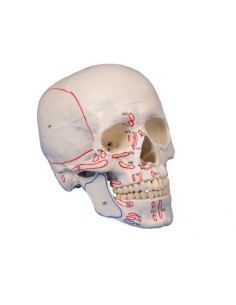

Crâne classique transparent, séparable en 3 parties, modèle anatomique 3B Scientific A20/T

3B scientifique, enseignement de luxe crâne BONElike™A283

Des modèles anatomiques détaillés pour tous les besoins

Du crâne en 22 parties à verrouillage magnétique aux modèles de colonne vertébrale, des modèles d'articulation aux modèles de cœur, chaque pièce de notre collection est conçue pour une immersion totale dans l'étude de l'anatomie humaine. Nos modèles, réalisés à partir de scans d'os réels, garantissent une expérience tactile authentique et une fidélité de poids presque identique aux originaux.

Indispensables aux étudiants comme aux professionnels, nos modèles anatomiques sont des outils pédagogiques qui permettent d'observer les structures anatomiques avec précision, en évitant les dissections ou les études invasives. Ils sont également utiles pour expliquer les pathologies aux patients, ce qui rend la communication plus efficace et permet de gagner un temps précieux.